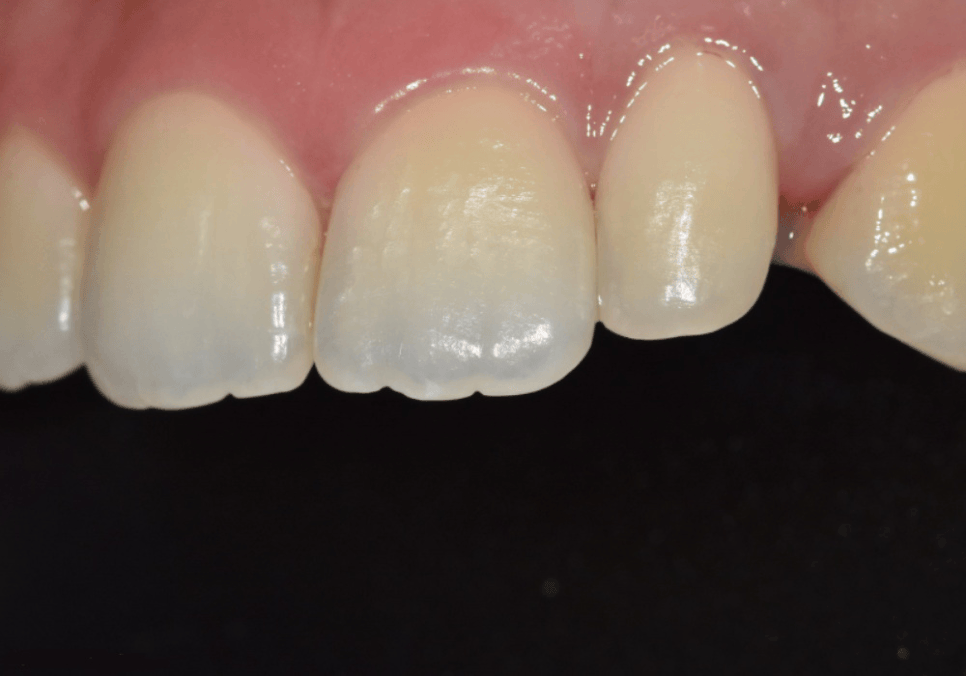

첫 번째 환자분은

앞니 바로 옆 치아의 크기가 상대적으로 작아

전체 앞니 비율이 무너져 보이던 상태였습니다.

이런 치아를

의학적으로는 왜소치라고 부르는데,

특히 양쪽에 동시에 있을 경우

가운데 앞니가 실제보다

훨씬 커 보이는 인상을 만들 수 있습니다.

이 환자분의 경우

앞니 네 개가 서로 촘촘하게 붙어 있어

작은 치아만 단독으로 키울

공간적인 여유가 거의 없었습니다.

230502

이 상태에서

옆 치아만 키우게 되면

앞니가 답답해 보이거나

전체가 앞으로 튀어나온 듯한

부자연스러운 느낌이 생길 수 있습니다.

그래서 이 환자분은

작은 치아를 키우는 치료가 아니라,

앞니 네 개의 크기를 다시 나누는 치료가

필요한 경우였습니다.

가운데 앞니는

눈에 띄지 않게 크기를 조금 줄이고,

옆 치아는 자연스럽게 키워

앞니 네 개가 비슷한 비율로 보이도록

4개의 라미네이트로 진행해드렸습니다.